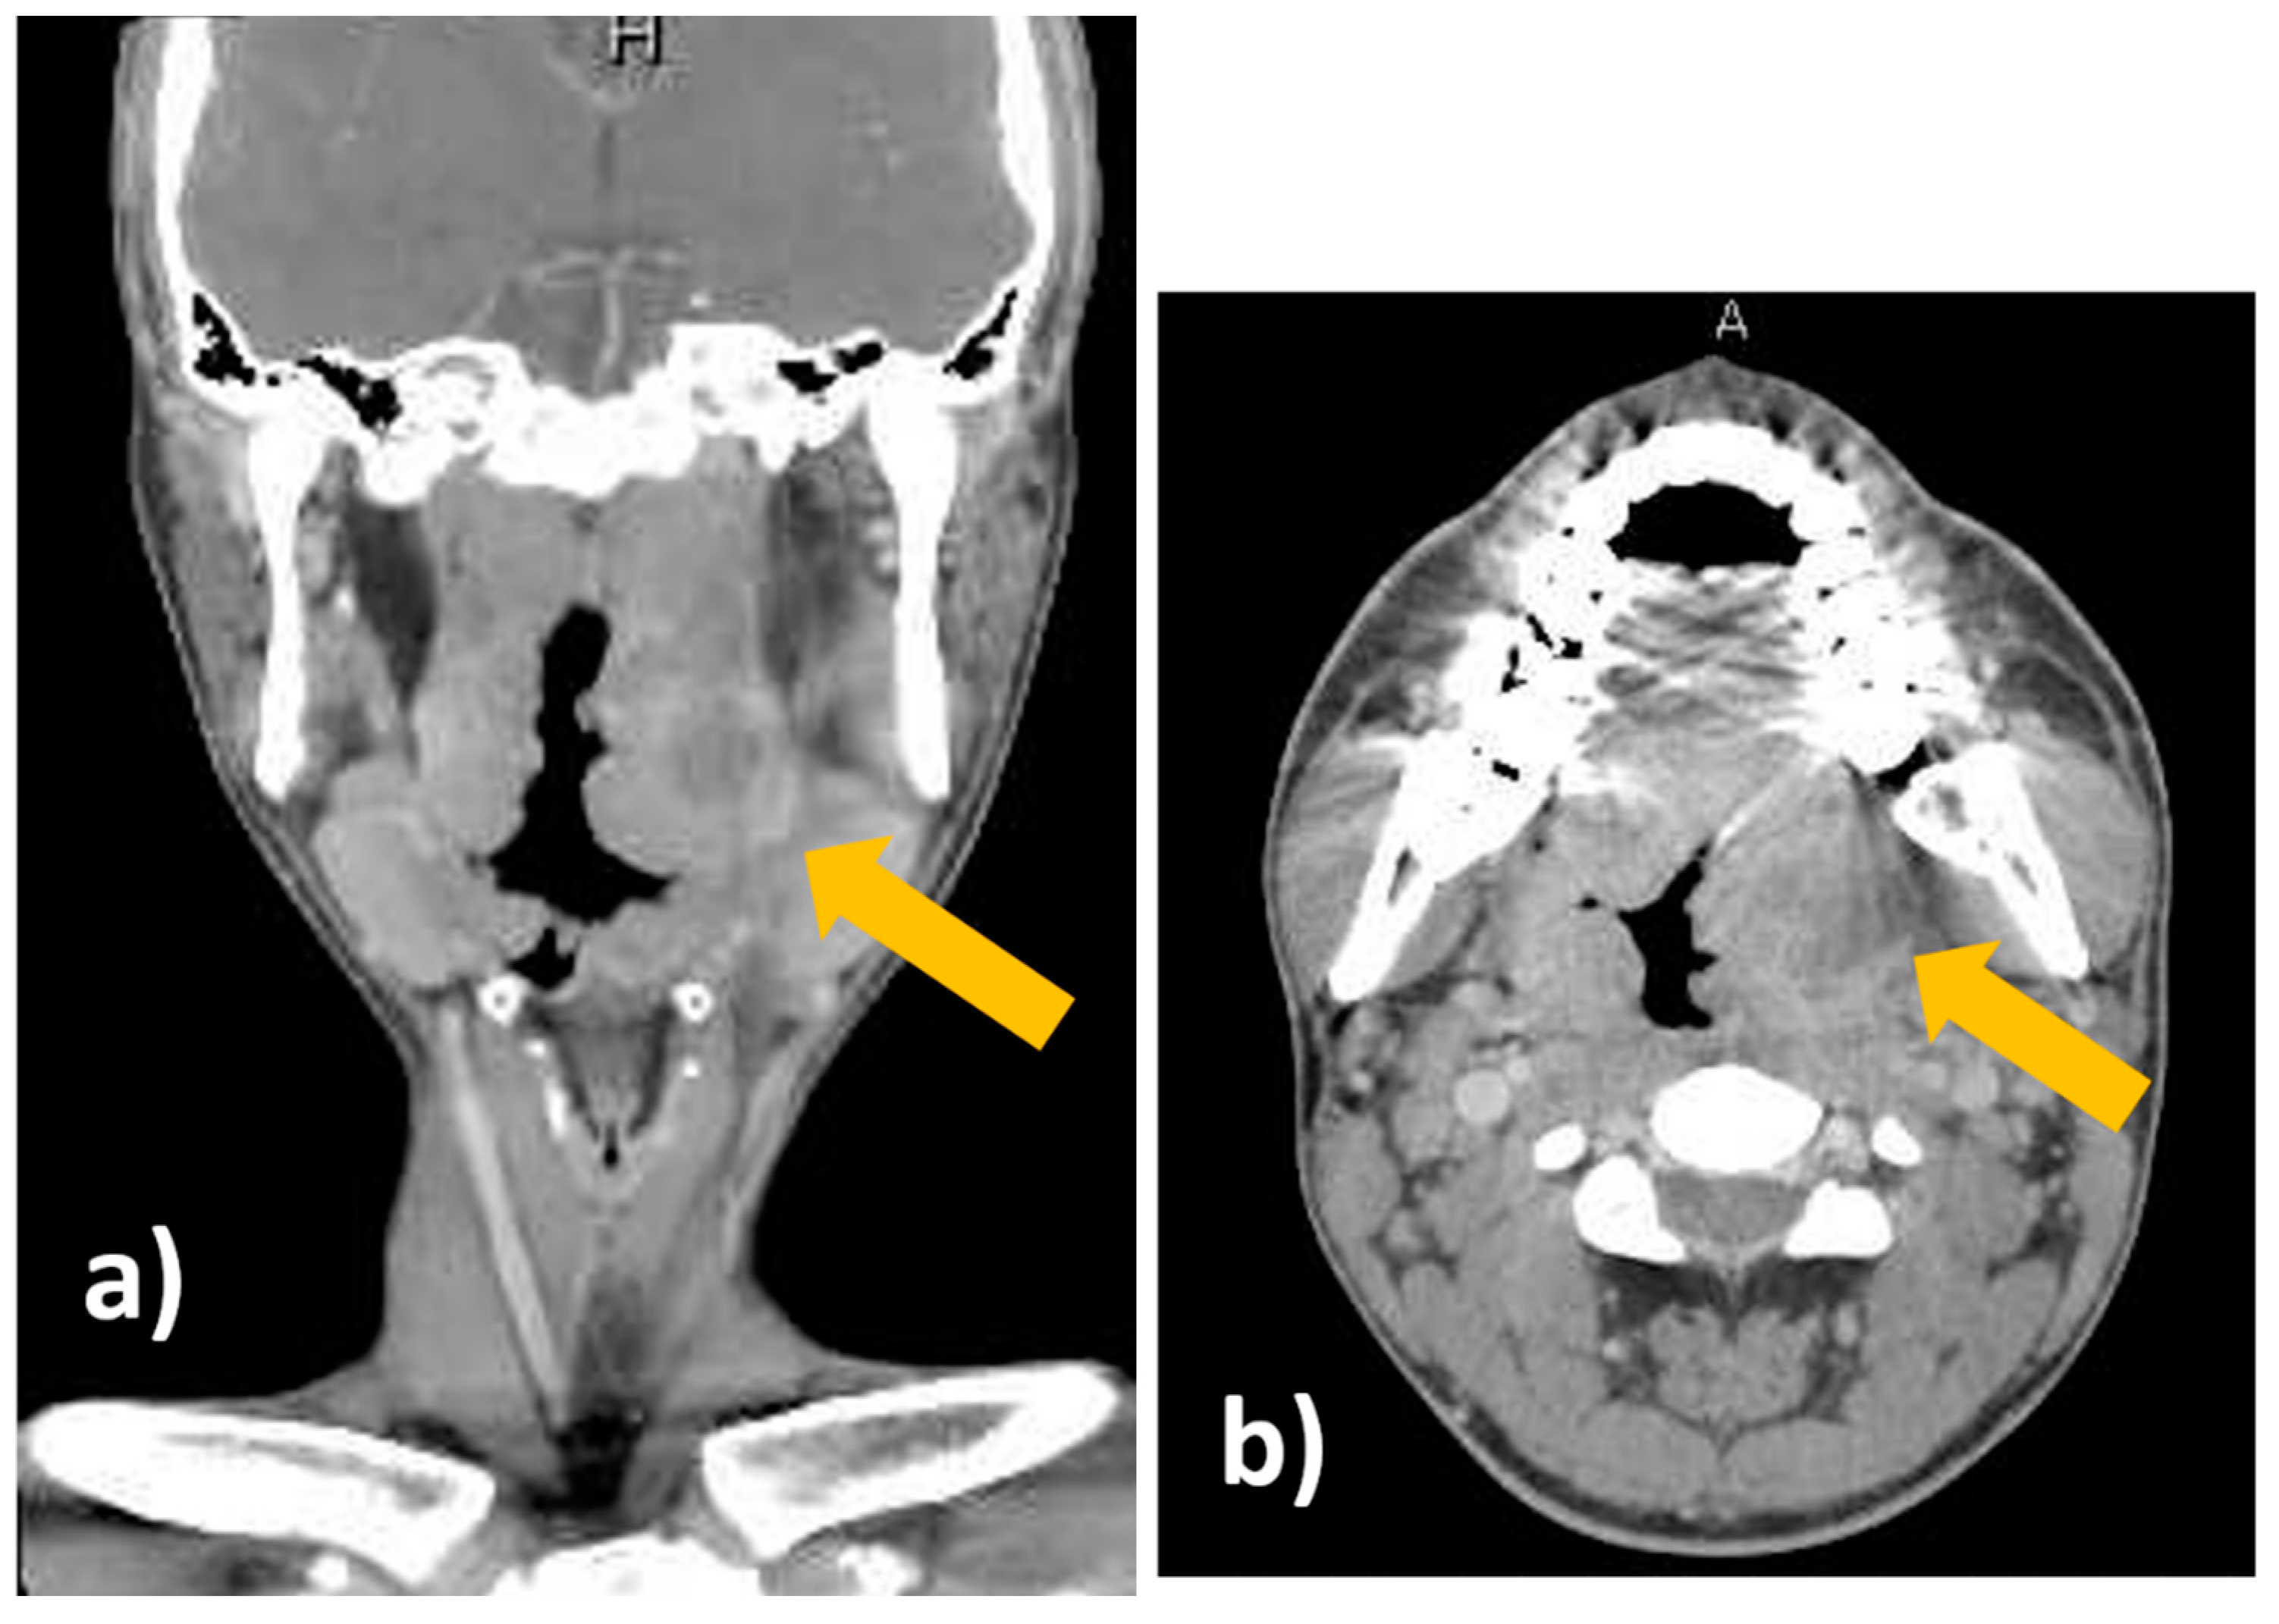

Figure 4.

Transoral pharyngeal ultrasonography (TOPU). (a) TOPU with B-mode. (b) TOPU with color Doppler. The left side of the image is the head side, and the right side is the foot side. TOPU shows the internal carotid artery (ICA) under the abscess at a depth of 30–40 mm and the external carotid artery (ECA) just under the abscess at a depth of 20–30 mm. The branches of the ECA surround the head side of the abscess. The tip of the needle is inserted at the center of the abscess in the hypoechoic space. The vertical green dotted line indicates the direction in which the needle advances; this guiding line system is incorporated in the ultrasound machine (Aplio500). (c) Schematic image. The periphery of the abscess is indicated by the red circle. It is easy to differentiate between the ICA and ECA because the branch arteries are visualized along with the ECA.